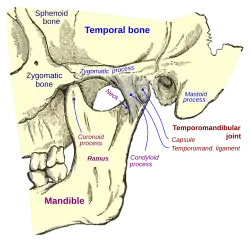

Anatomy and physiology

Temporomandibular joints

The temporomandibular joints are the dual articulation of the mandible with the skull. Each TMJ is classed as a "ginglymoarthrodial" joint since it is both a ginglymus (hinging joint) and an arthrodial (sliding) joint,[41] and involves the condylar process of the mandible below, and the articular fossa (or glenoid fossa) of the temporal bone above. Between these articular surfaces is the articular disc (or meniscus), which is a biconcave, transversely oval disc composed of dense fibrous connective tissue. Each TMJ is covered by a fibrous capsule. There are tight fibers connecting the mandible to the disc, and loose fibers which connect the disc to the temporal bone, meaning there are in effect 2 joint capsules, creating an upper joint space and a lower joint space, with the articular disc in between. The synovial membrane of the TMJ lines the inside of the fibrous capsule apart from the articular surfaces and the disc. This membrane secretes synovial fluid, which is both a lubricant to fill the joint spaces, and a means to convey nutrients to the tissues inside the joint. Behind the disc is loose vascular tissue termed the "bilaminar region" which serves as a posterior attachment for the disc and also fills with blood to fill the space created when the head of the condyle translates down the articular eminence.[42] Due to its concave shape, sometimes the articular disc is described as having an anterior band, intermediate zone and a posterior band.[43] When the mouth is opened, the initial movement of the mandibular condyle is rotational, and this involves mainly the lower joint space, and when the mouth is opened further, the movement of the condyle is translational, involving mainly the upper joint space.[44] This translation movement is achieved by the condylar head sliding down the articular eminence, which constitutes the front border of the articular fossa.[35] The function of the articular eminence is to limit the forwards movement of the condyle.[35] The ligament directly associated with the TMJ is the temporomandibular ligament, also termed the lateral ligament, which really is a thickening of the lateral aspect of the fibrous capsule.[35] The stylomandibular ligament and the sphenomandibular ligament are not directly associated with the joint capsule. Together, these ligaments act to restrict the extreme movements of the joint.[45]